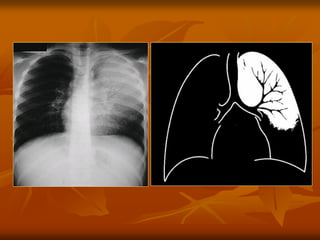

X QUANG PHUØ PHOÅI CAÁP

 Haäu quaû cuûa söï öù dòch trong moâ keõ

cuûa phoåi,vaø neáu naëng hôn thì dòch

traøn vaøo pheá nang.

 Hình X quang cuûa phuø phoåi tuøy thuoäc

vaøo möùc ñoä dòch naøy:thay ñoåi töø hình

môø maøu kính ñuïc cho ñeán hình ñuïc

daïng caùnh böôùm.